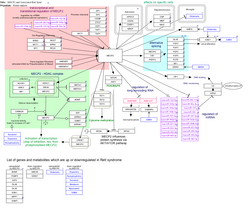

imgi_153_250px-IrinotecanPathway_WP229.png

imgi_164_250px-NicotineDopaminergic_WP1602.png

imgi_184_250px-Wikipathway_Deadenylation-dependent_mRNA_decay.png

imgi_187_250px-WP3584.png